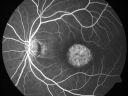

69 Year Old Woman Normal Fluorescein Angiogram874 views69-year-old woman OD 20/50 - OS 20/30 ATYPICAL PHOTOPSIAS